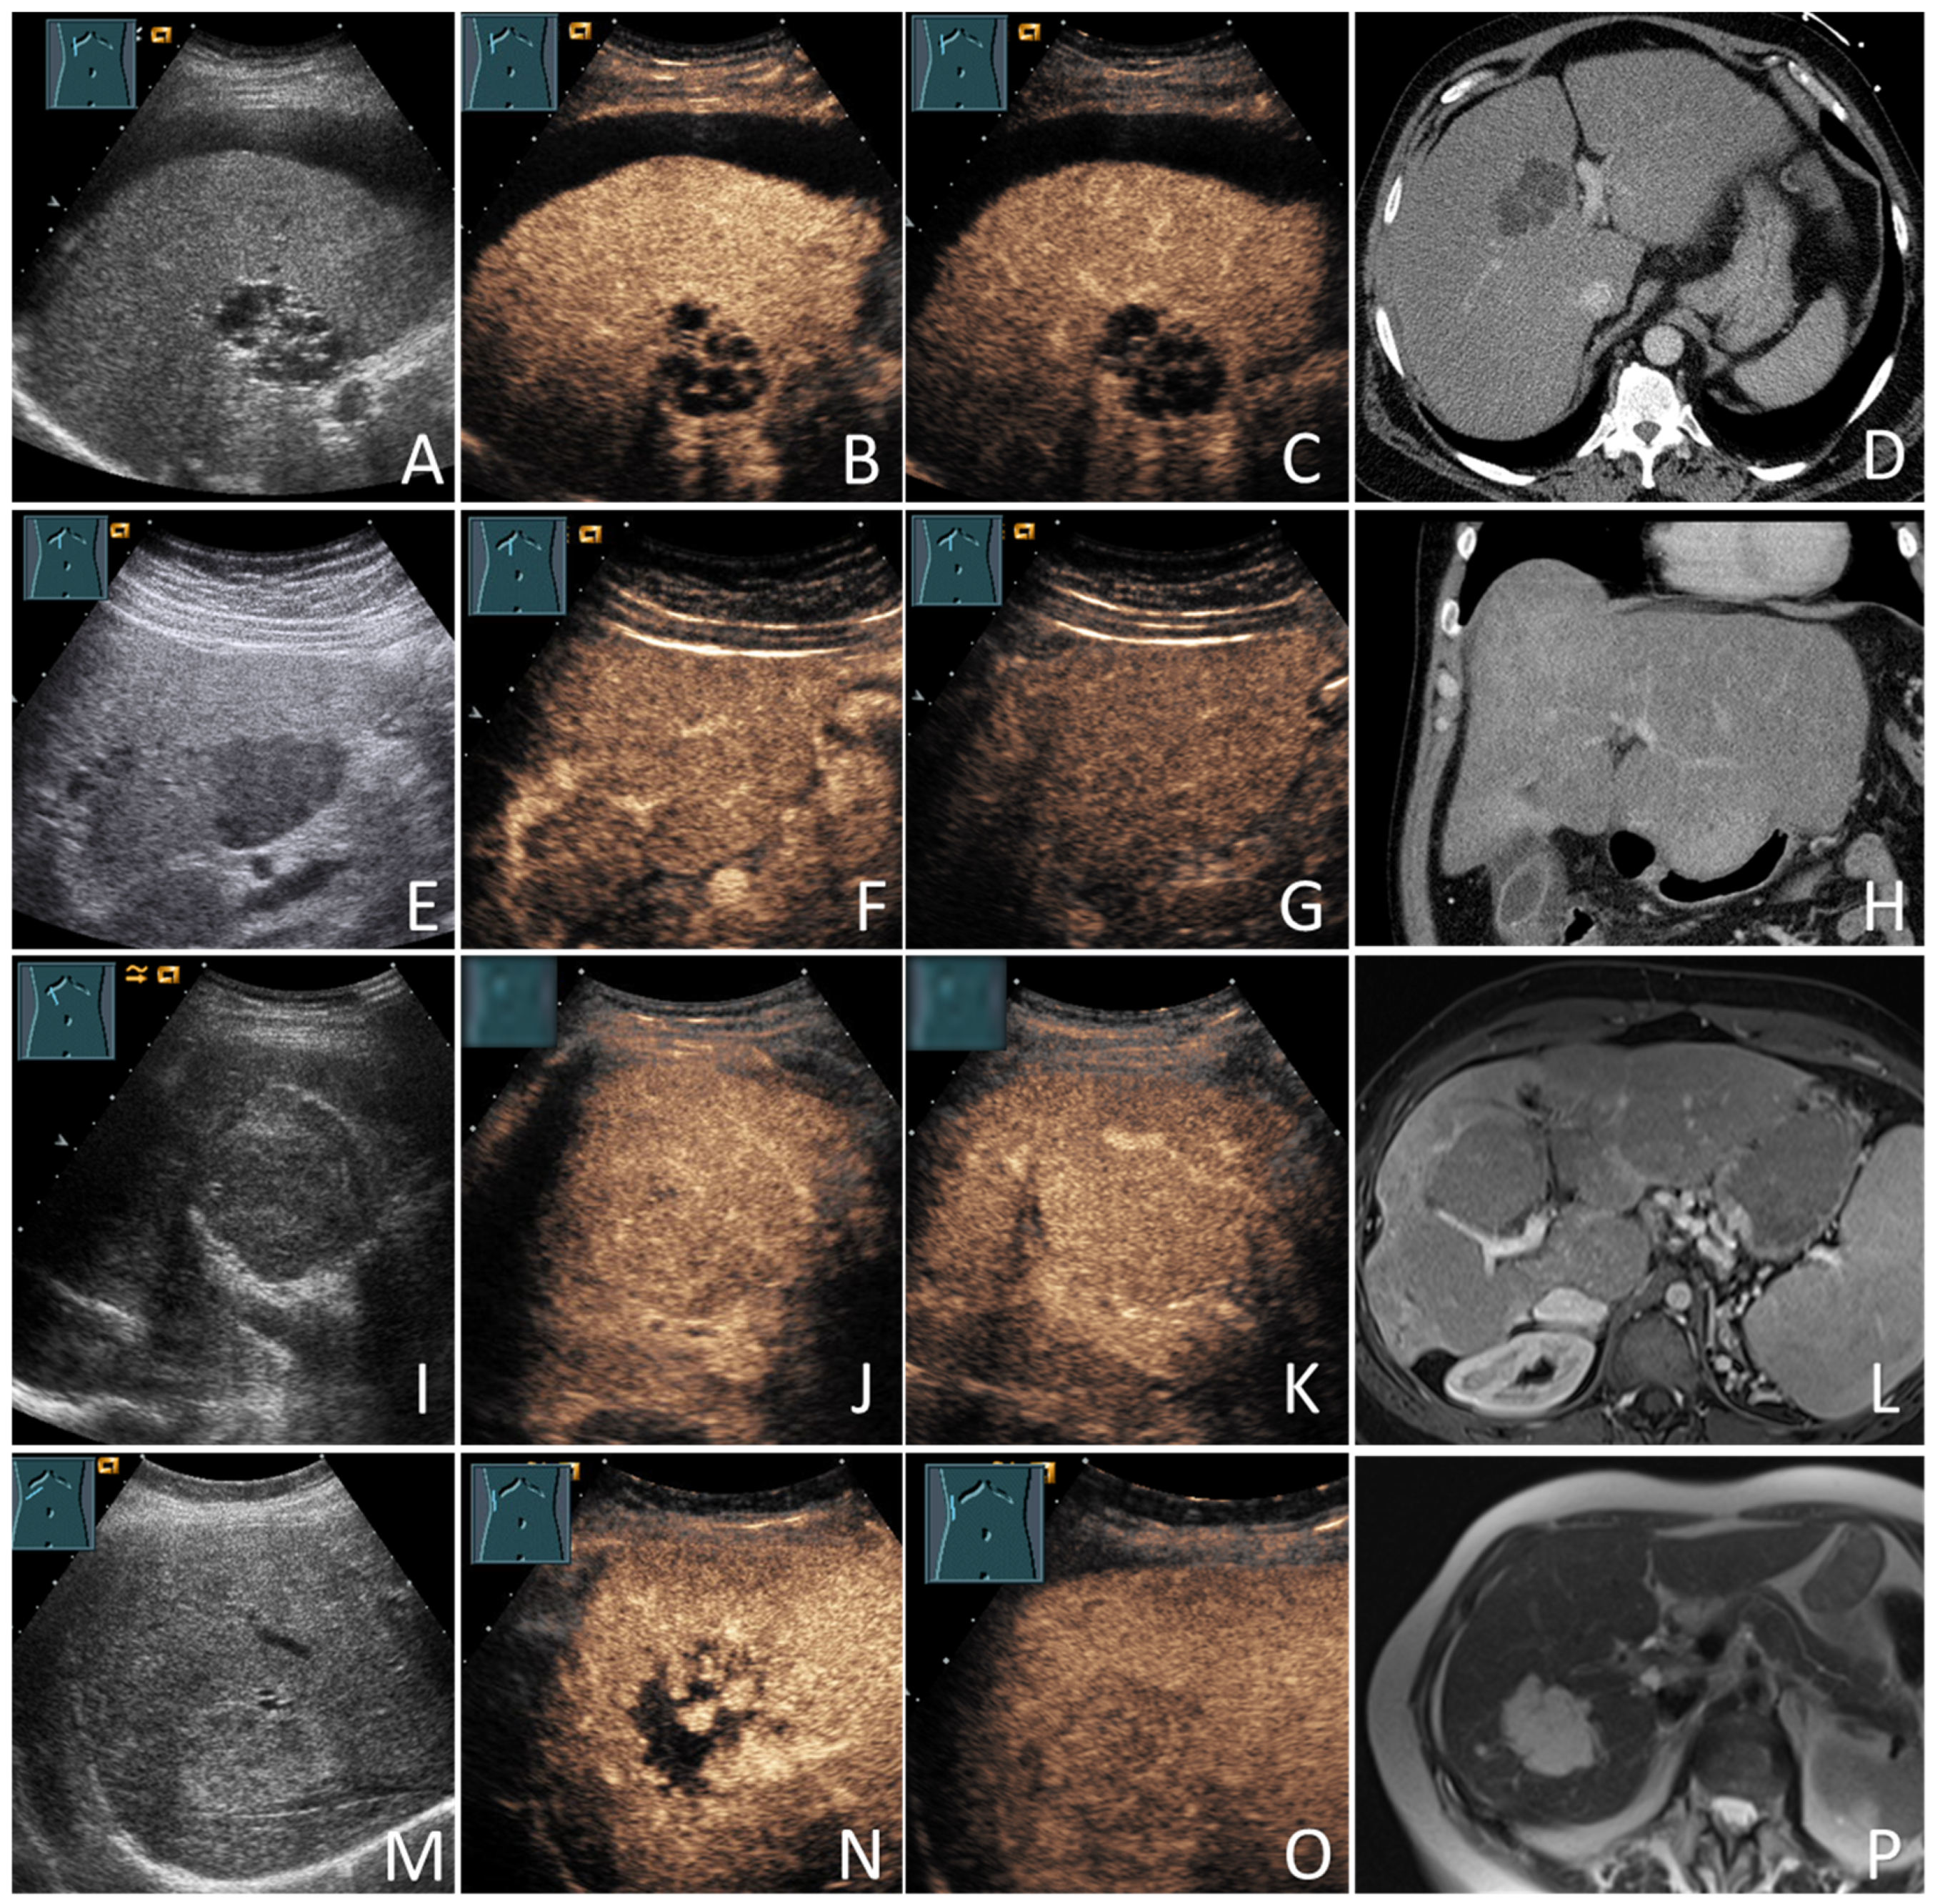

2.4. US and CEUS Examinations

2.5. Cross-Sectional Imaging